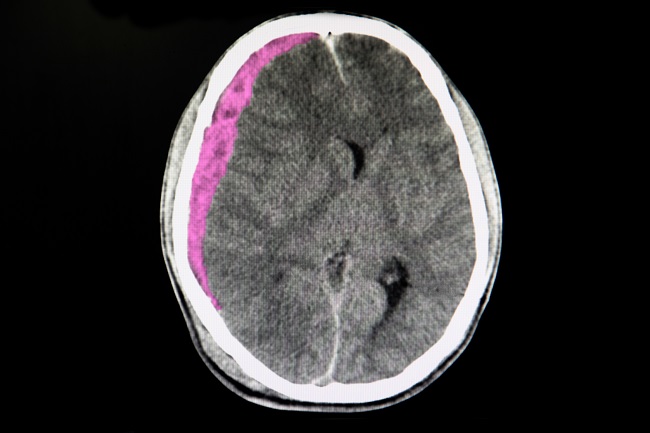

Pasien dengan SDH dapat dilakukan tata laksana non operatif jika dari hasil pemeriksaan CT scan kepala didapatkan ketebalan perdarahan kurang dari 10 mm dan pergeseran garis tengah atau midline shift kurang dari 5 mm.[2,3]

Indikasi tata laksana operatif pada SDH traumatik akut dipertimbangkan dengan pemeriksaan CT scan kepala dan tidak dari pemeriksaan GCS, yang meliputi:

- Ketebalan perdarahan >10 mm

- Pergeseran garis tengah atau midline shift >5 mm[2,3]